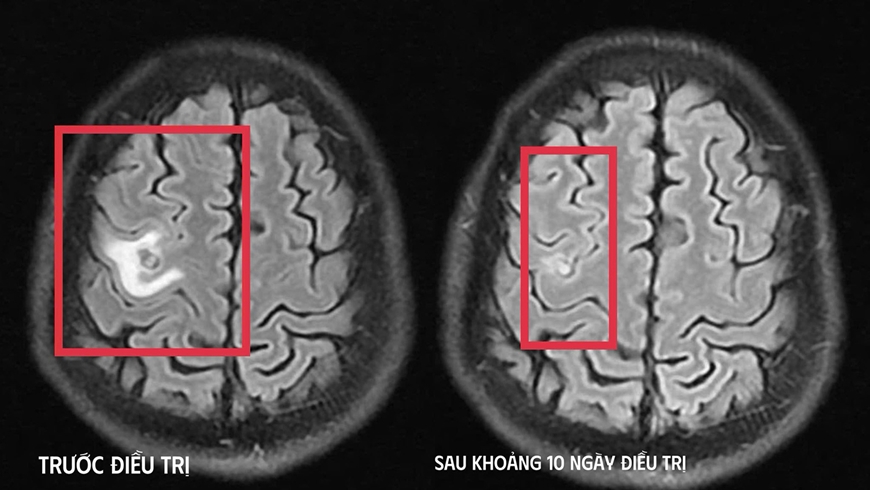

Bệnh nhân được chụp cộng hưởng từ (MRI) sọ não, phát hiện tổn thương dạng nang nhỏ tại thùy trán trái, kích thước khoảng 11 x 7mm, xung quanh có phù não nhẹ. Hình ảnh này hướng nhiều đến tổn thương do ký sinh trùng hơn là u não nguyên phát. Bệnh nhân được chỉ định xét nghiệm kháng thể kháng sán dây chó cho kết quả dương tính, giúp khẳng định chẩn đoán tổn thương não do ký sinh trùng.

Sau khi xác định nguyên nhân, bệnh nhân được điều trị nội khoa theo phác đồ, kết hợp kiểm soát triệu chứng và theo dõi sát diễn biến thần kinh. Sau khoảng 10 ngày điều trị nội trú, tình trạng bệnh nhân cải thiện rõ rệt, hết tê tay, không còn xuất hiện cơn co giật, không đau đầu hay chóng mặt, toàn trạng ổn định. Người bệnh được cho ra viện và tiếp tục điều trị ngoại trú đủ liệu trình kéo dài 4 tuần.